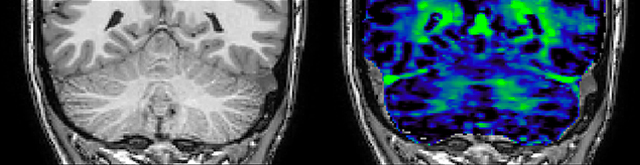

QSM elition Kames algorithm

QSM based on a Compressed SENSE multi-echo SWI.